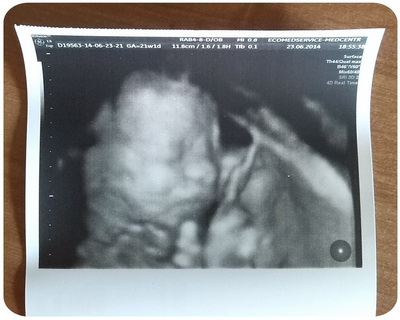

Одного товарища удалось сфотографировать. :)